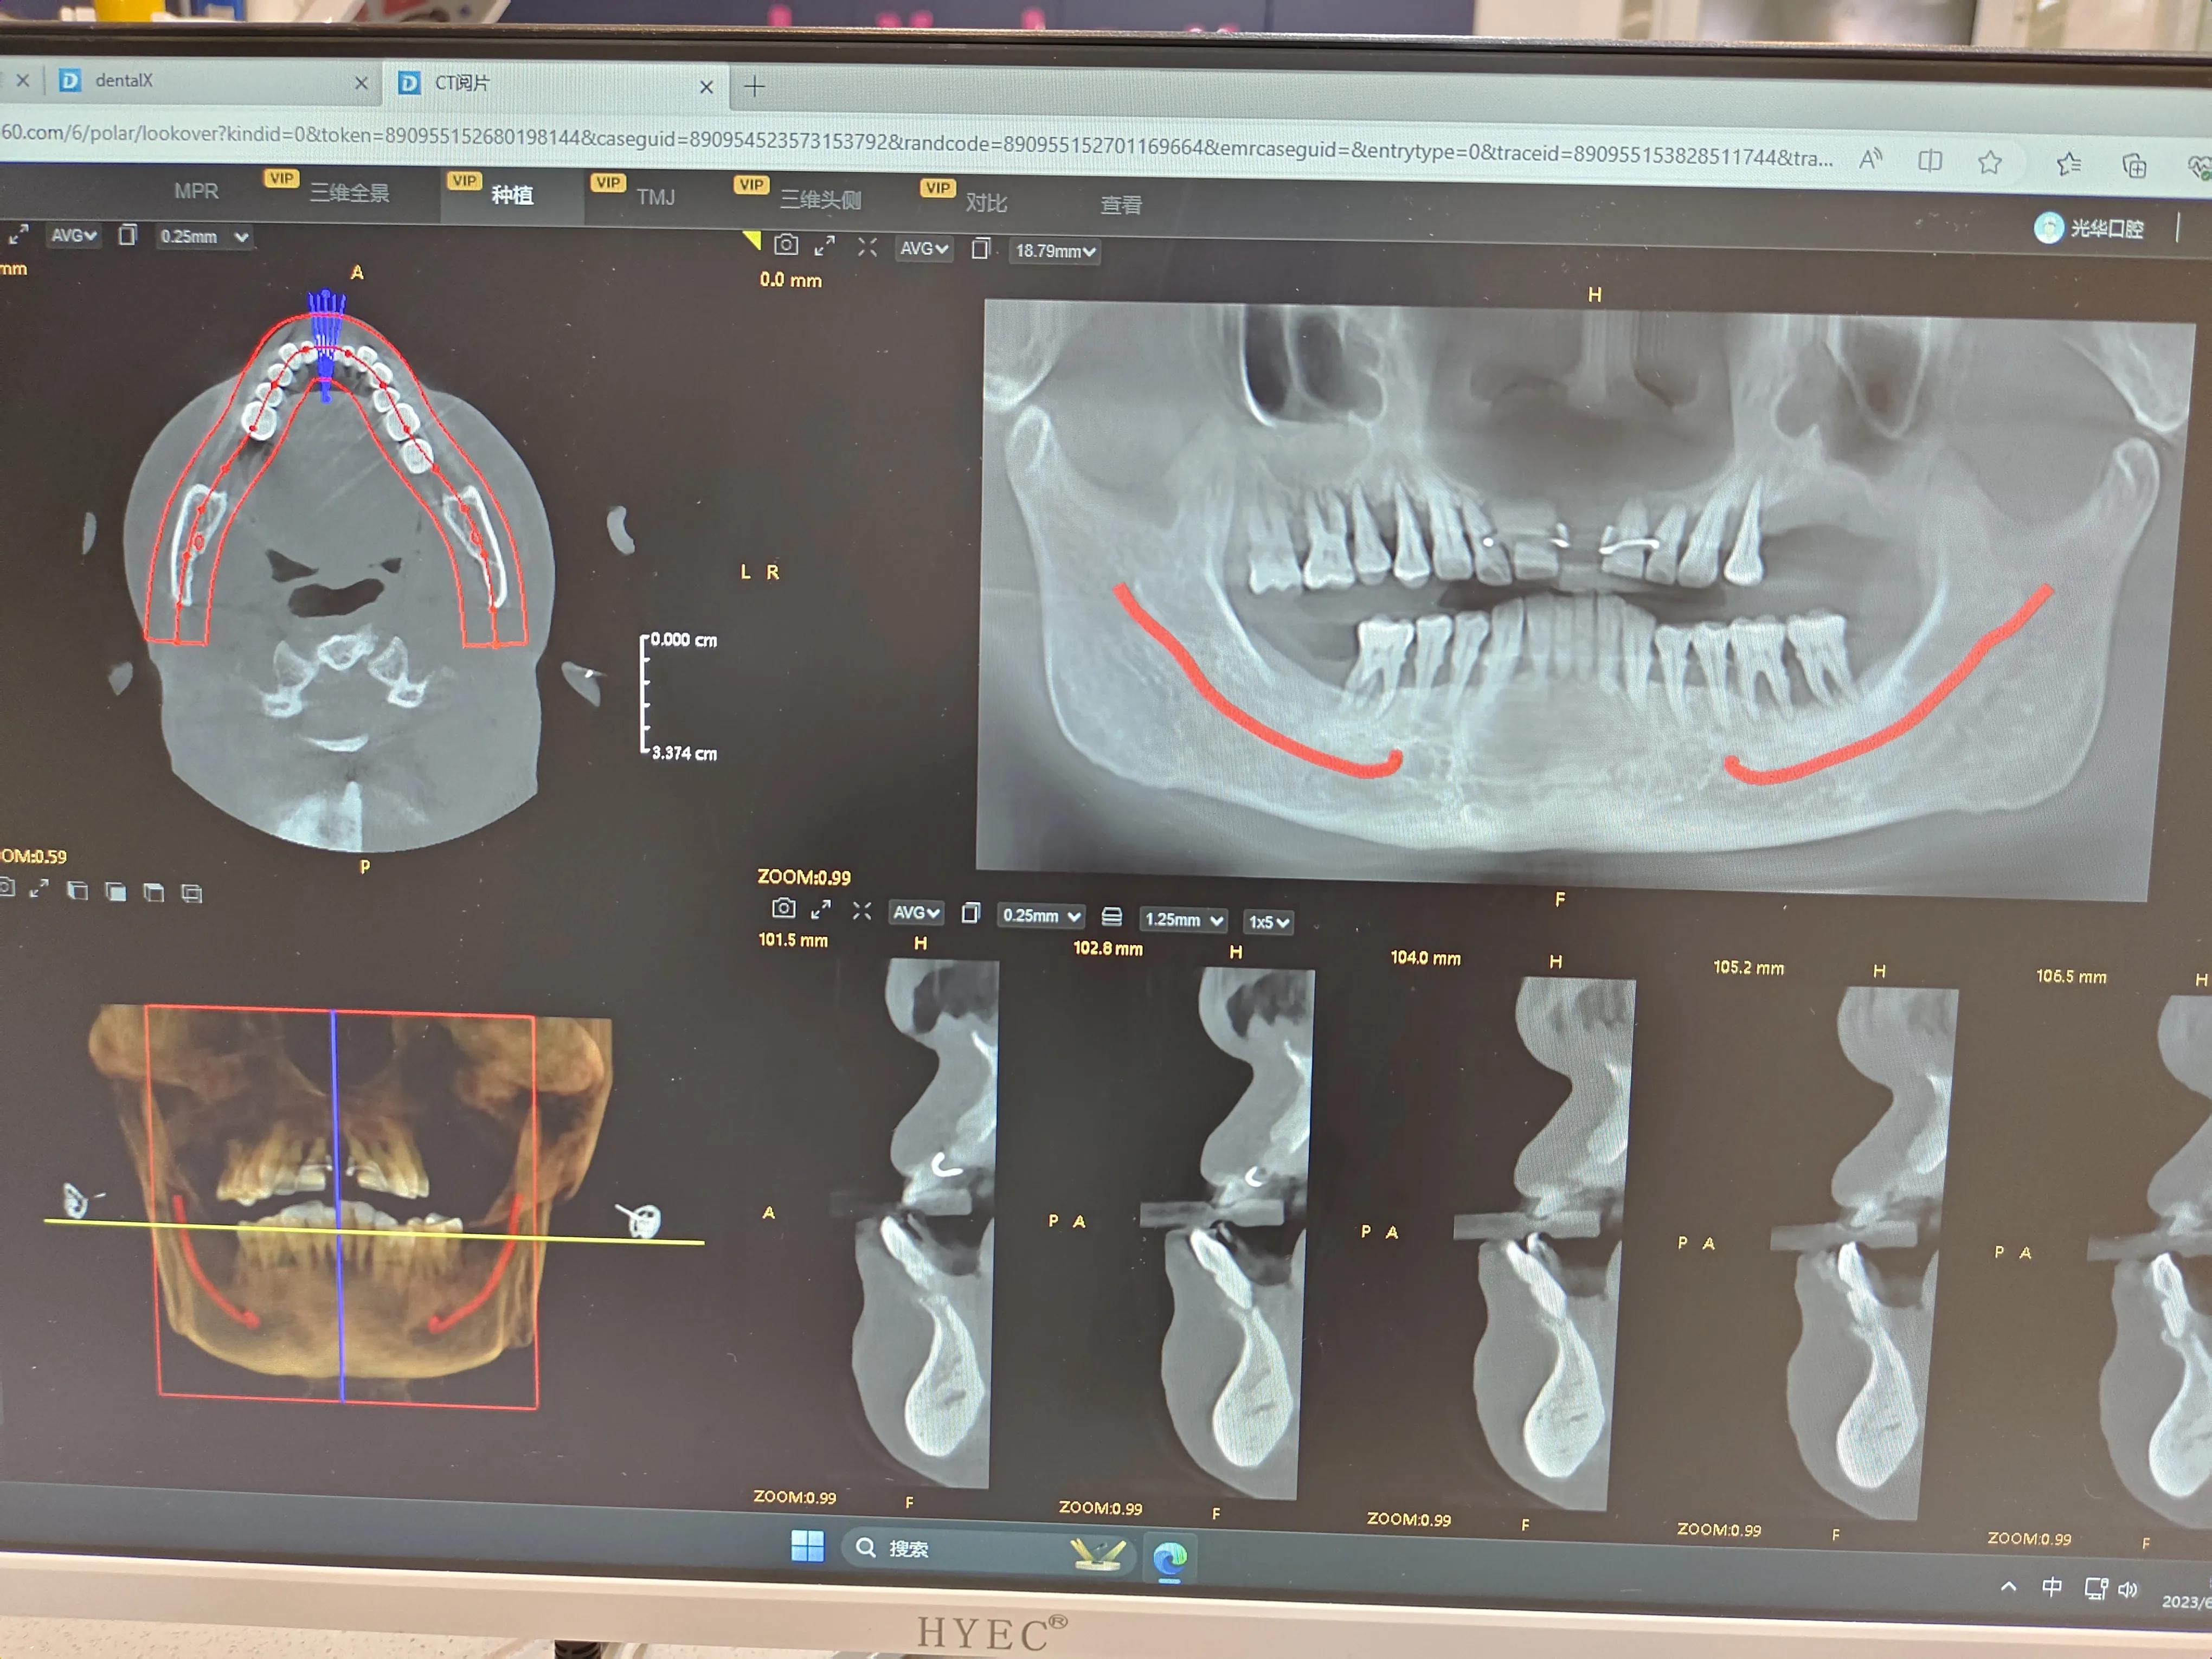

我牙齿拍的CT

我的牙龈萎缩厉害